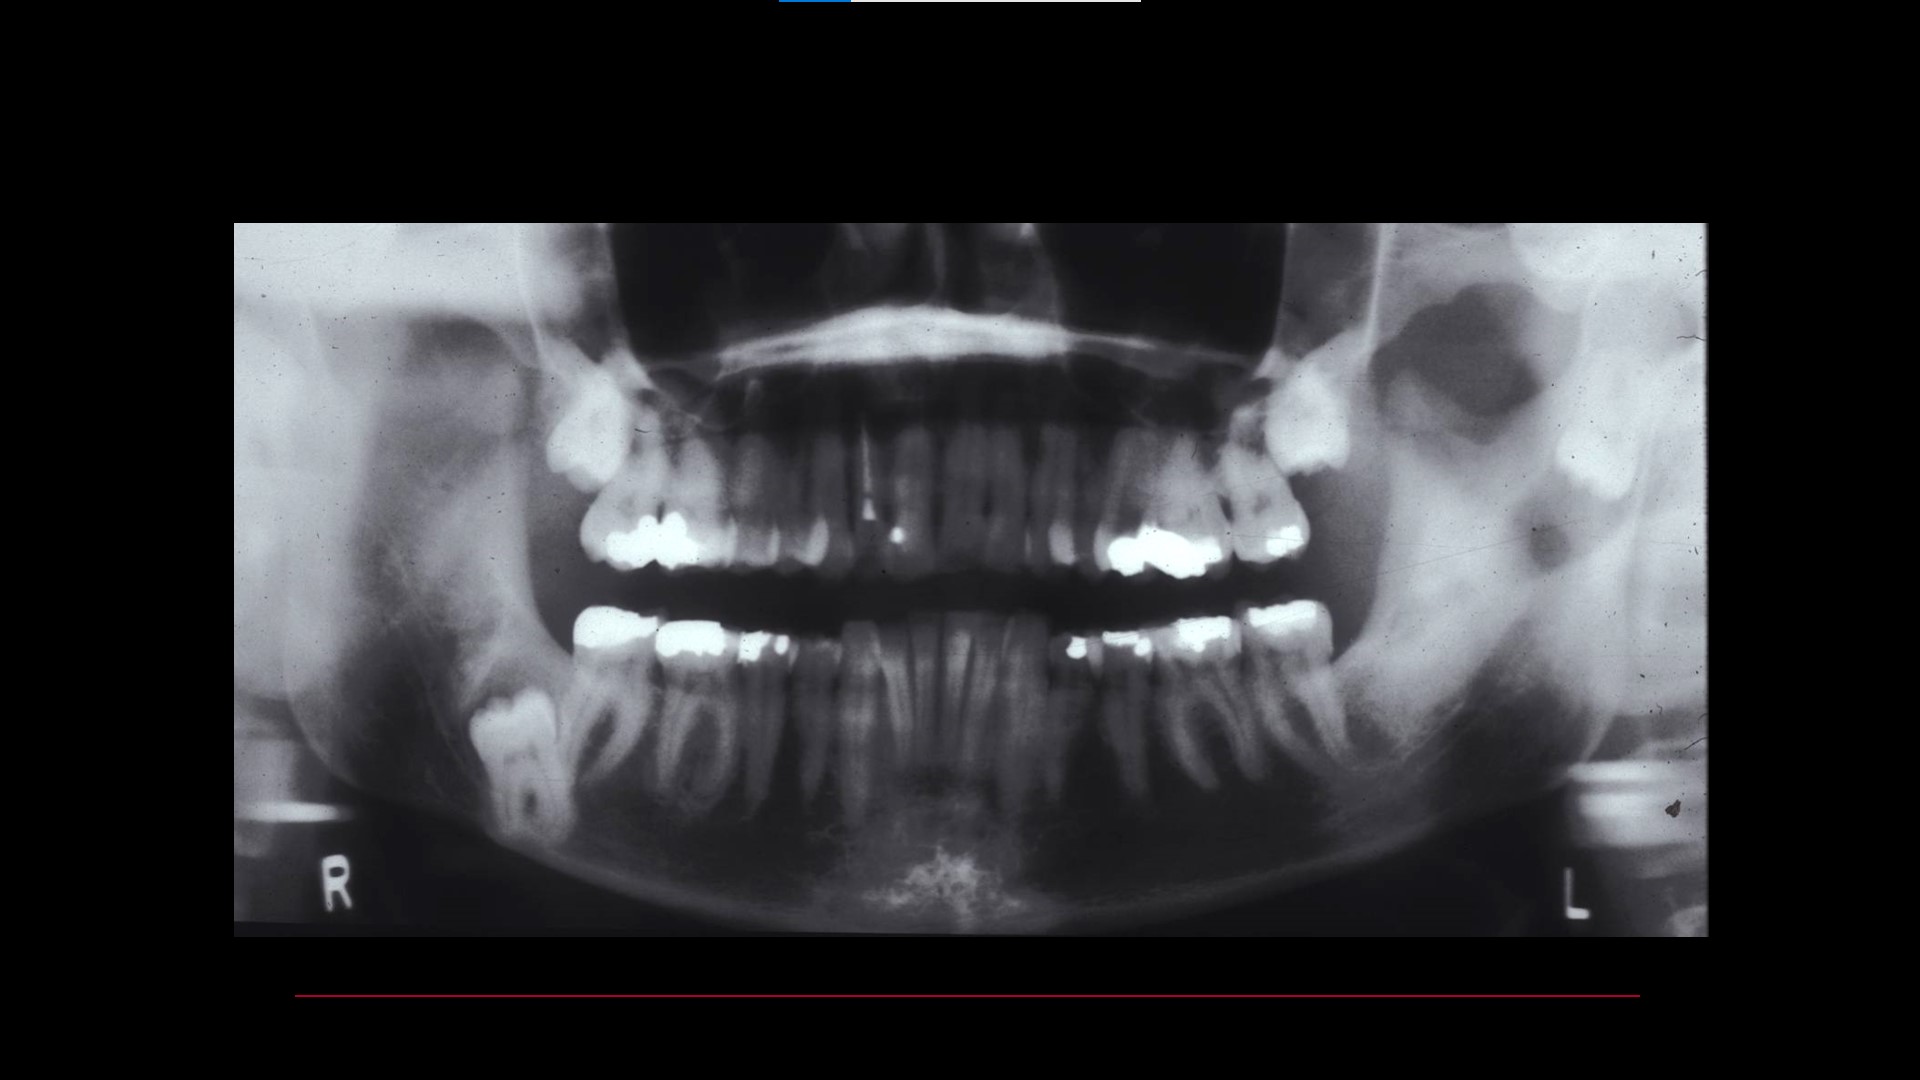

Impacted teeth